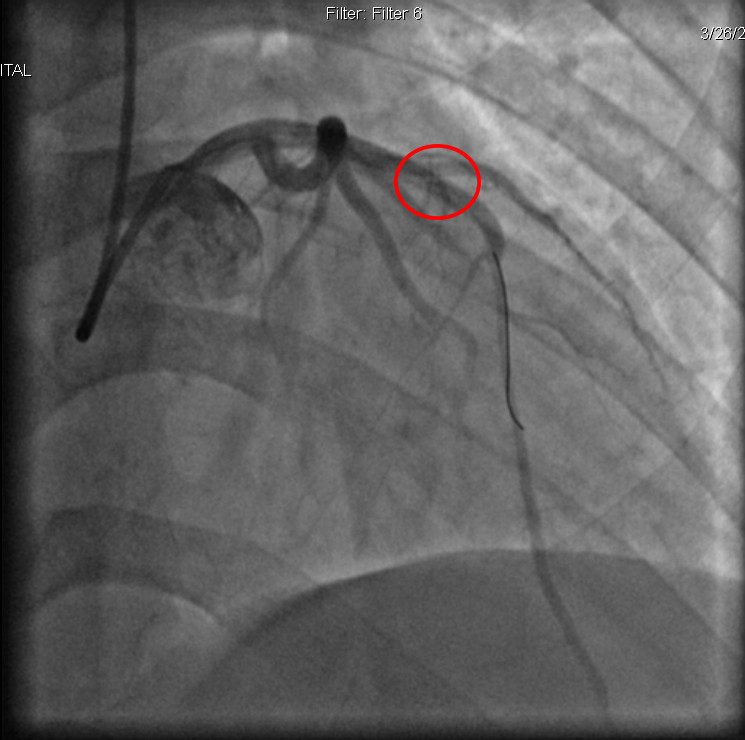

| Hình ảnh phim chụp sau can thiệp động mạch được tái thông - Ảnh BVCC |

Tại Bệnh viện Đa khoa tỉnh Phú Thọ, người bệnh được làm các xét nghiệm, điện tâm đồ, siêu âm tim và được chẩn đoán nhồi máu cơ tim cấp. Các bác sĩ đã chỉ định chụp và can thiệp động mạch vành qua da. Kết quả chụp mạch vành cho thấy hẹp 99% LAD1, ngay lập tức người bệnh được can thiệp nong bóng, đặt một stent tại vị trí động mạch bị tắc để tái thông dòng chảy.

Sau can thiệp, tình trạng người bệnh đã cải thiện rõ rệt: hết khó thở, hết đau ngực. Sau 3 ngày điều trị, người bệnh hồi phục tốt và được ra viện.